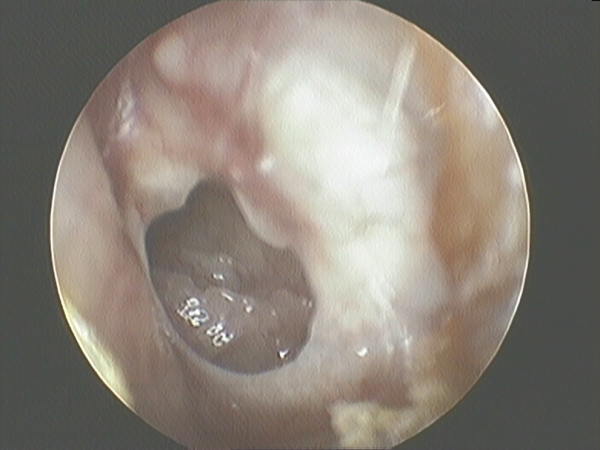

The inclusion criteria included perforation size >25% of the surface of the pars tensa of the TM, absence of infection or otorrhea at surgery, and lack of spontaneous closure at the 6-month follow-up. The exclusion criteria were the presence of cholesteatoma, attical pathology, perforation without clear margins, wet appearance of the mucosa in the tympanic cavity, presence of an acute infection, ear discharge in the 3 months before surgery, or signs of ossicular inconsistency (Figure 1).

Figure 1

Perforated tympanic membrane.